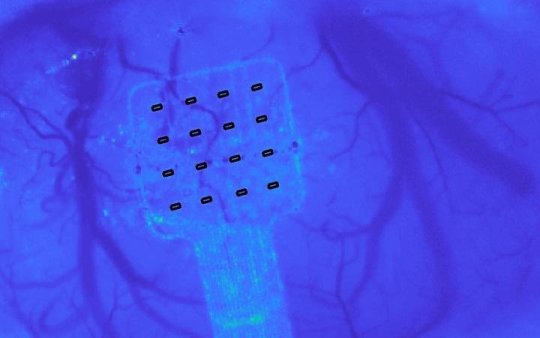

The new device was developed thanks to a collaboration between three Graphene Flagship Partners (IMB-CNM, ICN2 and ICFO) and adapted for brain recordings together with biomedical experts at IDIBAPS. This new technology moves away from electrodes and uses an innovative transistor-based architecture that amplifies the brain’s signals in situ before transmitting them to a receiver. The use of graphene to build this new architecture means the resulting implant can support many more recording sites than a standard electrode array. It is slim and flexible enough to be used over large areas of the cortex without being rejected or interfering with normal brain function. The result is an unprecedented mapping of the low frequency brain activity known to carry crucial information about different events, such as the onset and progression of epileptic seizures and strokes.

For neurologists this means they finally have access to some clues that our brains only whisper. This ground-breaking technology could change the way we record and view electrical activity from the brain. Future applications will give unprecedented insights into where and how seizures begin and end, enabling new approaches to the diagnosis and treatment of epilepsy.

“Beyond epilepsy, this precise mapping and interaction with the brain has other exciting applications,” explains José Antonio Garrido, one of the leaders of the study working at Graphene Flagship Partner ICN2. “In contrast to the common standard passive electrodes, our active graphene-based transistor technology will boost the implementation of novel multiplexing strategies that can increase dramatically the number of recording sites in the brain, leading the development of a new generation of brain-computer interfaces.” Taking advantage of ‘multiplexing’, this graphene-enabled technology can also be adapted by some of the same researchers to restore speech and communication. ICN2 has secured this technology through a patent that protects the use of graphene-based transistors to measure low-frequency neural signals.